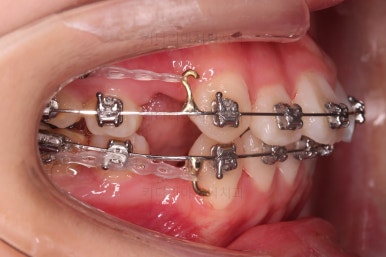

초진 시, 입 안의 모습입니다.

치아가 많이 삐뚤어요.

공간이 부족해서 앞니가 앞으로 많이 뻐드러졌고, 삐뚤한 양상 때문에 덧니가 되었네요.

어금니 맞물림도 좋지 못한 앵글씨 2급 부정교합 상태였어요.